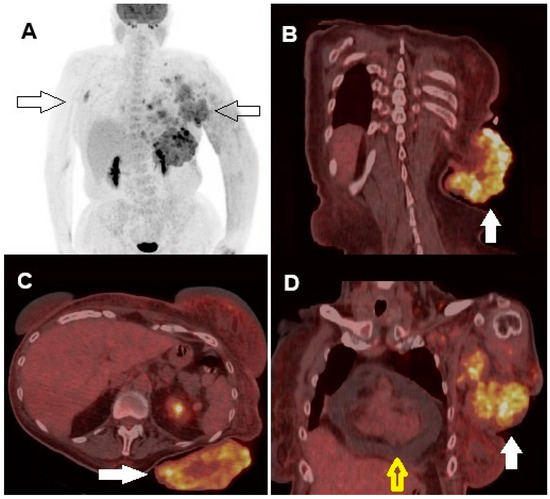

It Looks Like a Zebra but Is Not: [18F]FDG PET/CT in a Giant Cutaneous Malignant Melanoma Mimicking Squamous Cell Carcinoma

Proietti, I.; Azzella, G.; Dirzu, D.; Di Cristofano, C.; Bagni, O.; Potenza, C.; Filippi, L. It Looks Like a Zebra but Is Not: [18F]FDG PET/CT in a Giant Cutaneous Malignant Melanoma Mimicking Squamous Cell Carcinoma. Diagnostics 2024, 14, 2860. https://doi.org/10.3390/diagnostics14242860